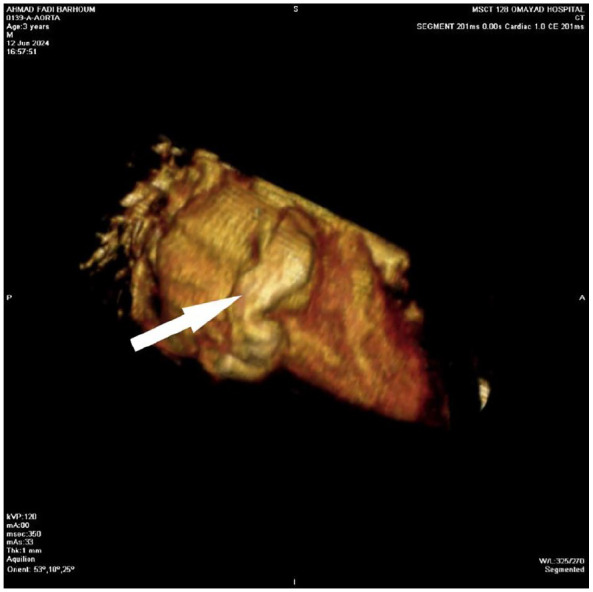

Kawasaki disease (KD), a febrile vasculitis primarily affecting young children under 5, is commonly associated with coronary artery complications. This report describes the case of a 2.5-month-old infant presenting with a persistent 15-day fever, initially misidentified as pharyngitis and otitis media. Laboratory tests indicated significant leukocytosis, thrombocytosis, and increased C-reactive protein (CRP) levels. Echocardiography revealed coronary artery dilation and pericardial effusion, confirming a KD diagnosis. The infant received intravenous immunoglobulin (IVIG) and high-dose aspirin, which resolved the fever. Symptom recurrence necessitated additional IVIG and corticosteroid treatment. Subsequent imaging showed ongoing coronary dilation, emphasizing the risk of lasting vascular complications. This case underscores the diagnostic challenges of KD in infants, especially those with atypical presentations. Prompt diagnosis and treatment are critical to prevent serious complications such as coronary aneurysms. Healthcare providers should consider KD in infants with prolonged unexplained fevers to improve prognosis and minimize heart-related risks.